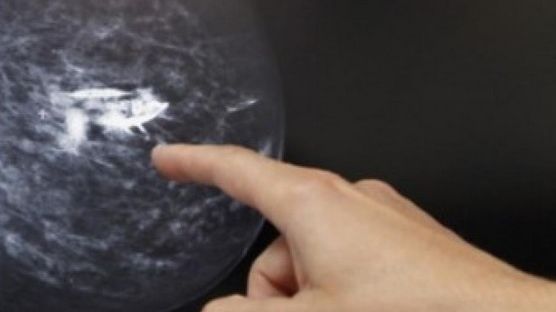

15 iul. 2016, 19:08ActualCe NU spun medicii despre mamografii. Tot ce trebuie să ştii despre screeningul pentru cancer

4 iun. 2015, 19:35ActualCum se poate reduce riscul apariţiei cancerului la sân? Recomandările medicilor

2 dec. 2009, 09:06Ultimele StiriMamografia ar putea să accelereze cancerul la sân, arată un nou studiu